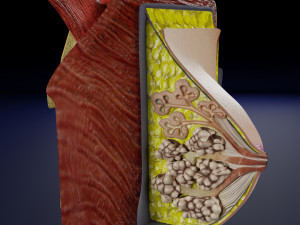

This is a 1:1 scaled model of right breast cut opened in sagittal plane to reveal its internal antomy and histology (schematic). The deeper parts and fascial layers are also depicted to give a very detailed approach to the model. The full layers starting from skin, nipple areola, till intercodtal muscles and ribs are also depicted.

breast mammary gland female chest wall anatomy human medical science reproductive genitalia muscle fascia milk nipple areola subcutaneous fatДо даного товару немає коментарів.